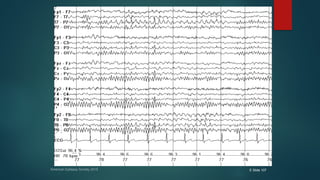

Generalized Interictal Epileptiform Discharges

๏ต Present in a bilateral symmetric fashion.

๏ต Generalized spike and slow waves consist of bilaterally

synchronous spikes followed by a slow wave of high

amplitude

๏ต Typically, the diffuse spike and slow wave often has

frontal predominance and may occur in rhythmic runs at

various frequencies

๏ต This electrographic pattern is consistent with the

diagnosis of generalized epilepsy.